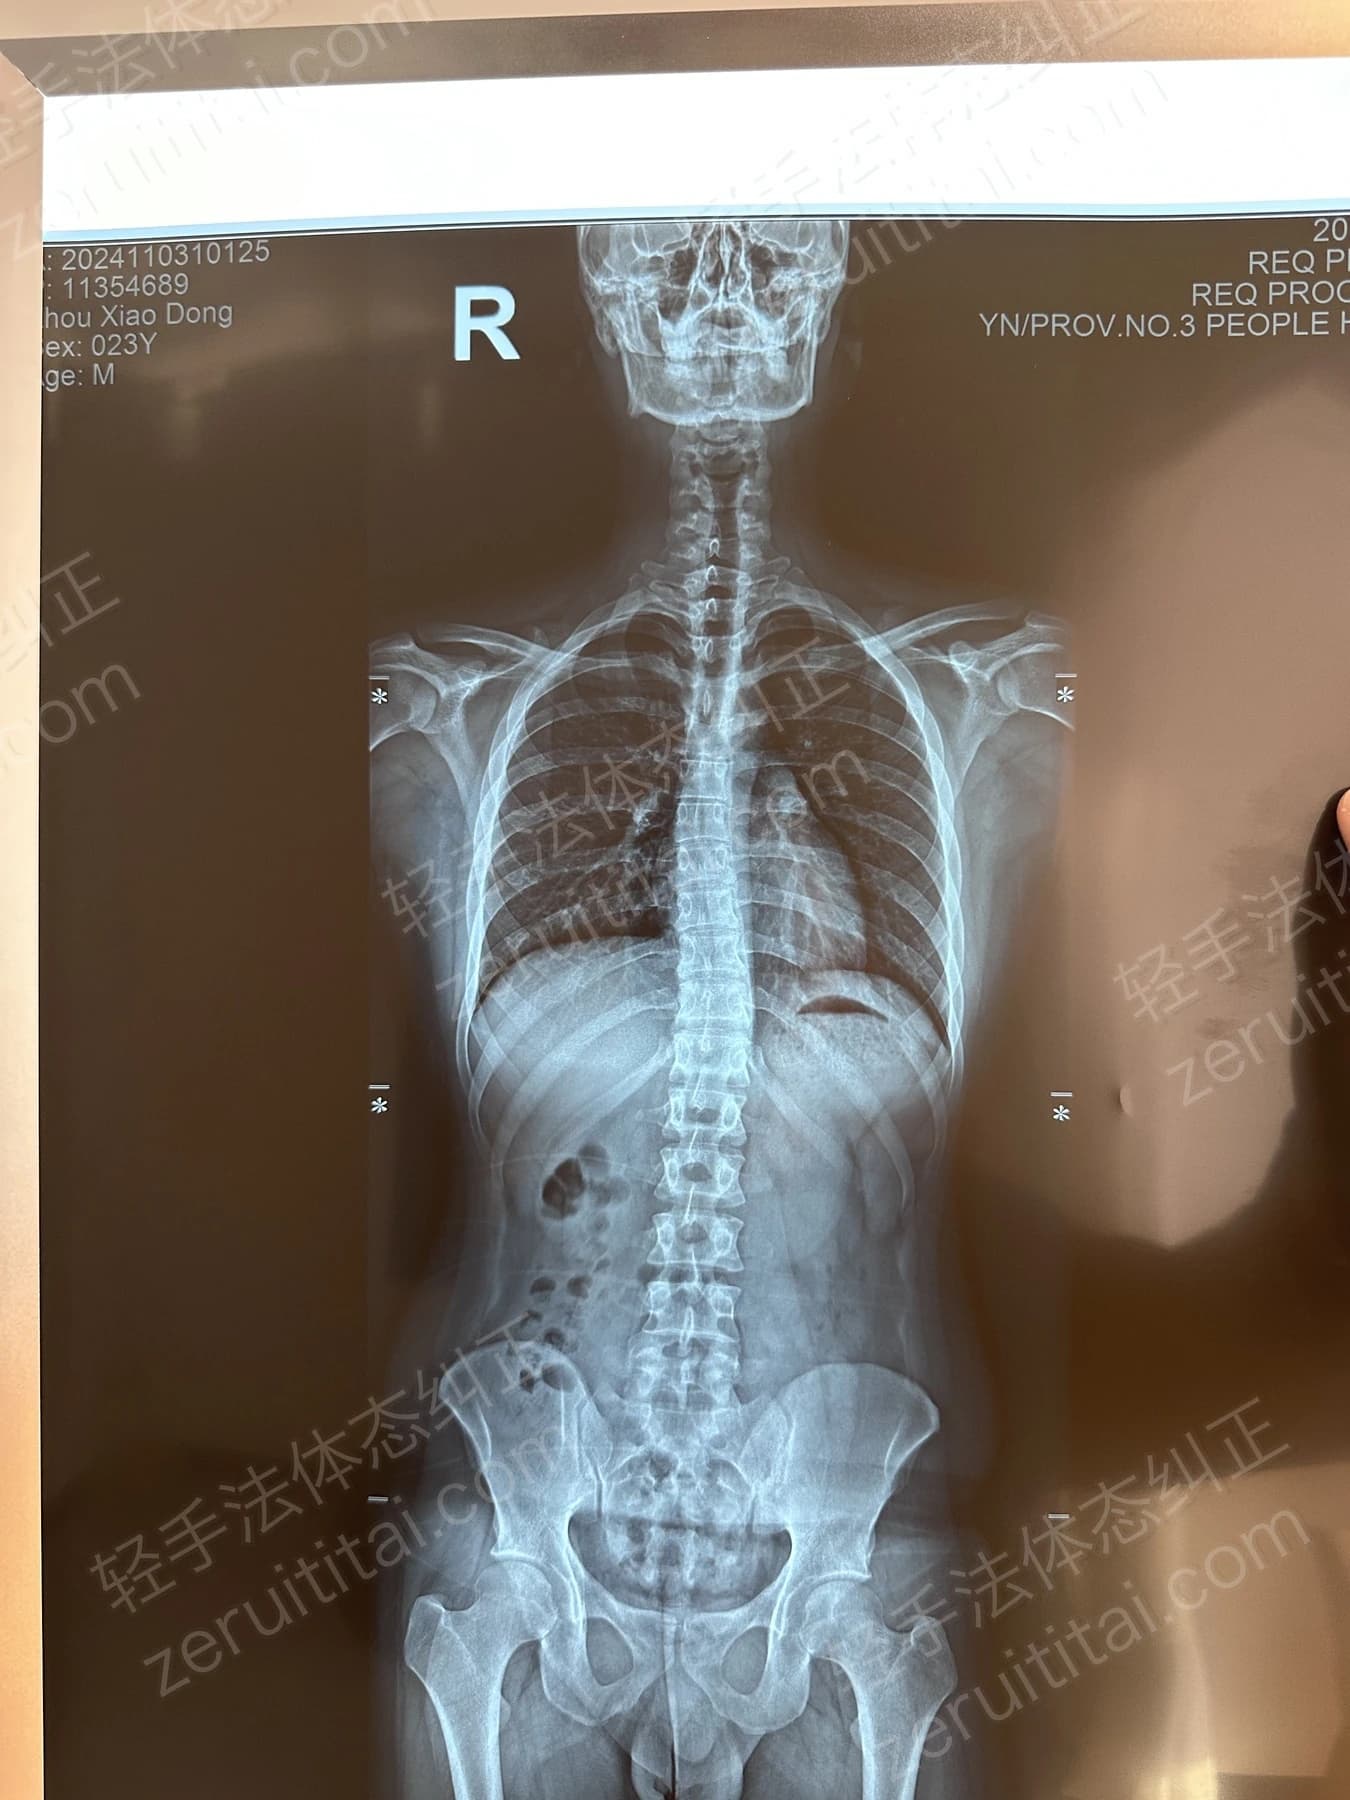

2023.12.16

第 5 次记录